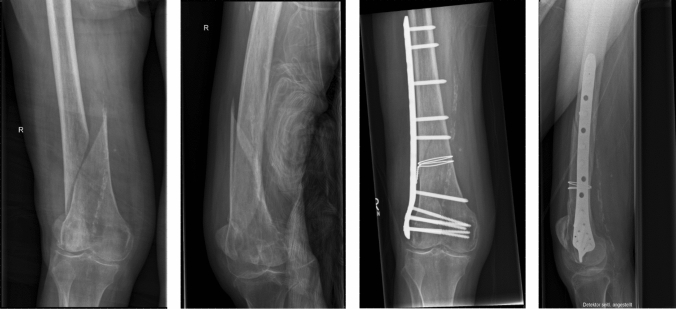

Fig. 1.

Clinical case of a 78-year-old woman with a 32-A2.3 distal femoral fracture. The fracture was surgically treated with a direct fracture repositioning using a double-looped wire cerclage and a retrograde inserted, polyaxially angular plate osteosynthesis